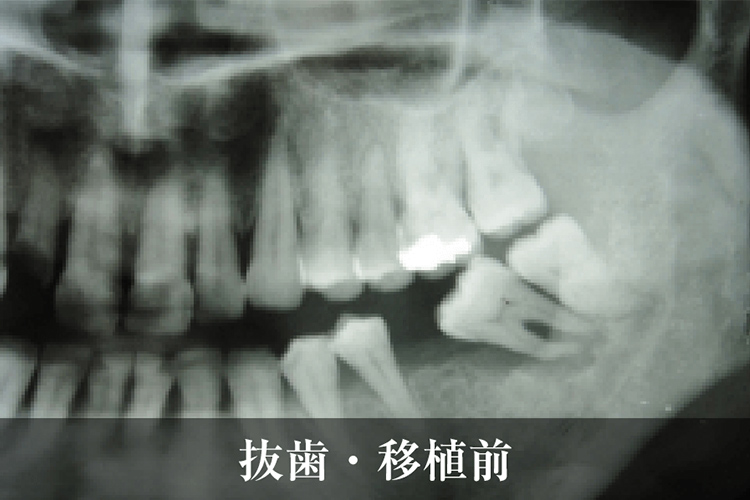

治療前

移植歯

移植後

補綴装着

抜歯・移植前

抜歯・移植後固定中

固定後・ブリッジ完成